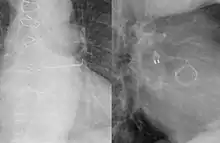

The Watchman is a one-time implant typically performed under general anesthesia with transesophageal echo guidance (TEE). Similar to a stent procedure, the device is guided into the heart through a flexible tube (catheter) inserted through the femoral vein in the upper leg. The implant is introduced into the right atrium and is then passed into the left atrium through a puncture hole.[6] These small iatrogenic atrial septal defects usually disappear within six months.[7][8] Once the position is confirmed, the implant is released and is left permanently fixed in the heart. The implant does not require open heart surgery and does not need to be replaced. Recovery typically takes twenty-four hours.[6]